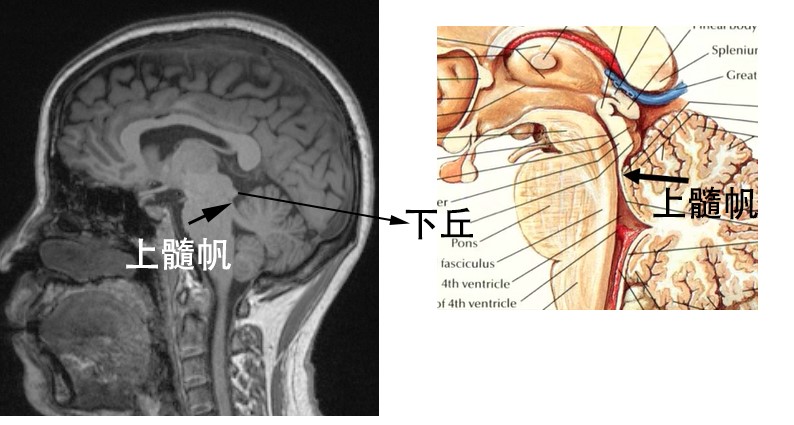

神经解剖外传——简单又不简单的滑车神经

让你过目不忘非常容易误诊小结构滑车钙化

神经解剖外传——简单又不简单的滑车神经